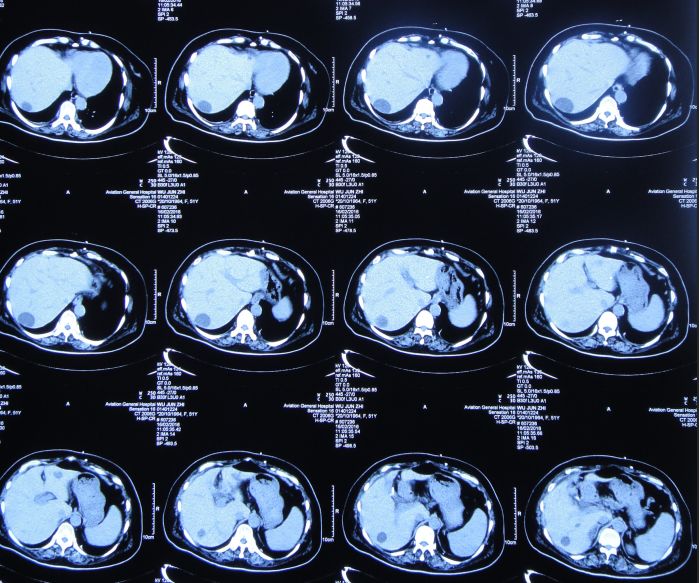

患者女,50岁,安徽省淮北市人。2014年12月14日,患者因高处坠落伤(2米左右)伤及头胸部及四肢,致昏迷,左耳、左鼻流血性液体,急诊前往安徽省淮南市潘集区某医院急查头CT显示左额叶脑挫伤、左侧颞骨凹陷性骨折、脑肿胀、颅内积气(图1);眼眶CT显示双侧眼眶内侧壁骨折(图2);胸部CT显示左侧肋骨骨折伴肺挫伤;右上肢X片显示右桡骨远端粉碎性骨折;左肩部X片显示左侧锁骨骨折。立即给予住院,保守治疗。

图1:2014年12月14日头CT:左额叶脑挫伤、左侧颞骨凹陷性骨折、脑肿胀、颅内积气